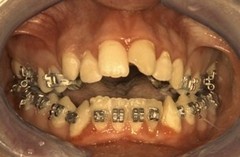

II Classe Iperdivergente morso aperto (Caso 2)

Casi Clinici pre - post Chirurgiia Ortognatodontica

casi trattati chirurgicamente dal Prof. Aldo Bruno Giannì